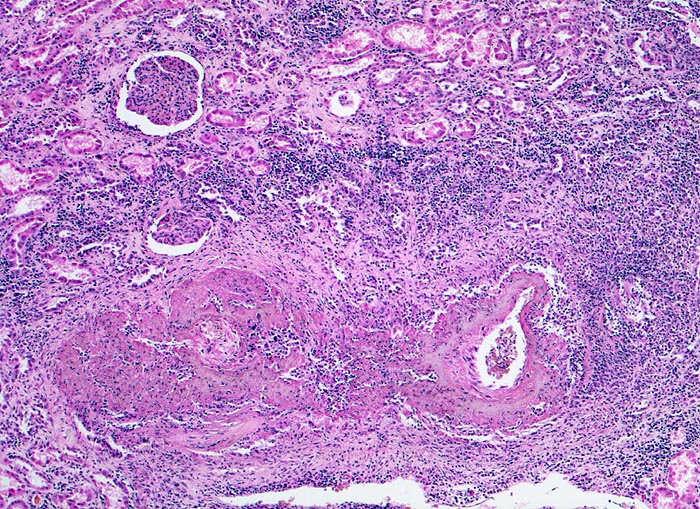

Befallen sind prärenale und grössere intrarenale Nierenarterienäste bei meist fehlender Beteiligung der Arteriolen und definitionsgemäss fehlendem Befall der glomerulären Kapillaren. Die betroffenen Gefässe zeigen segmentale transmurale oft durch Thrombosierung komplizierte Wandnekrosen mit initial granulozytenreichem Infiltrat. Im Verlauf werden die Nekrosen durch Granulations- und Narbengewebe organisiert. An grossen Arterien kann dies zu Knotenbildungen und Aneurysmata führen. Oft findet man in ein und demselben Gefäss frische Nekrosen neben reparativen Veränderungen und Narben. Das übrige Nierengewebe zeigt als Folge der Vaskulitis Kollapsglomerula, Infarkte und ischämische Tubulusatrophie mit begleitender interstitieller Fibrose und Entzündung.